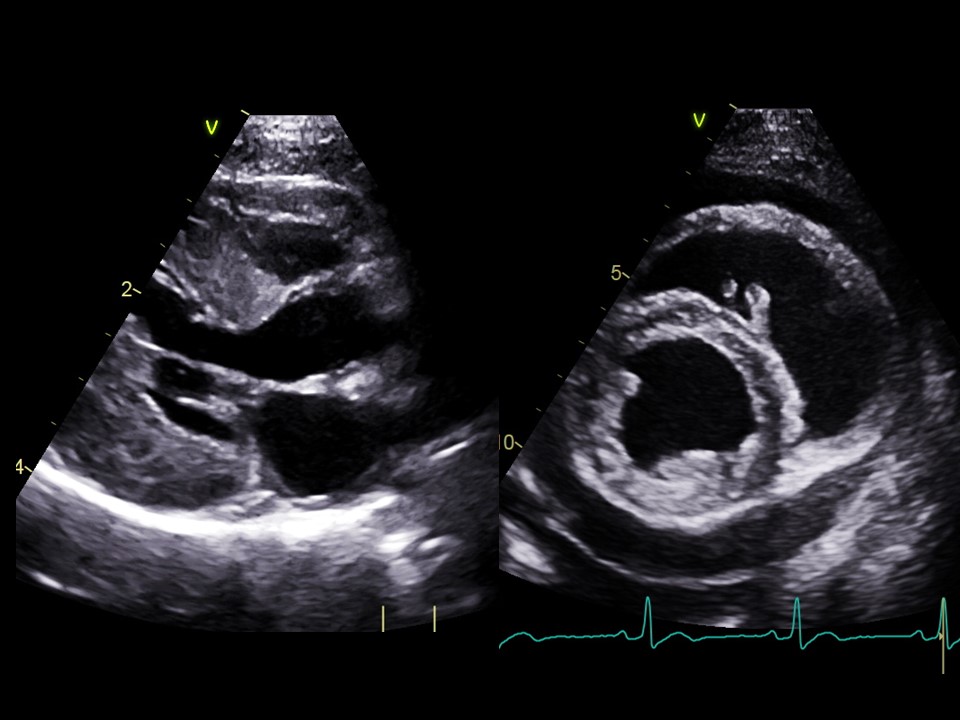

- Échocardiographie 2D et TM des principales cardiopathies congénitales

- Analyse d'images fixes et vidéos 2D/TM

- Échocardiographie 2D et TM des principales cardiopathies acquises